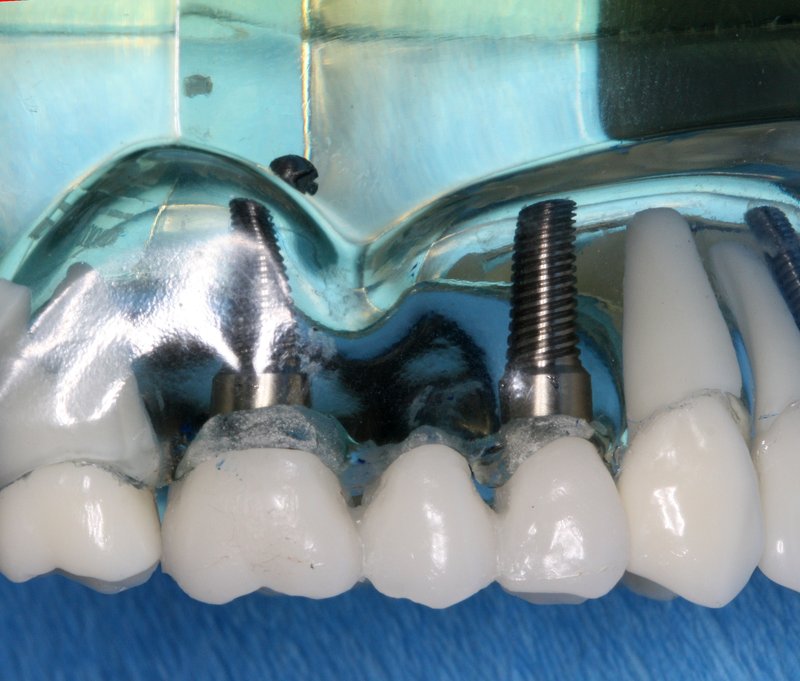

When several teeth are missing in the same area, multiple implants can be placed to support a fixed bridge or series of individual crowns. Rather than placing one implant per missing tooth, Dr. Tran strategically positions implants to provide maximum support with minimal surgery. This approach restores your ability to chew and speak naturally while preserving the bone structure that would otherwise deteriorate after tooth loss. Multiple implants are a durable, long-term alternative to removable partial dentures.